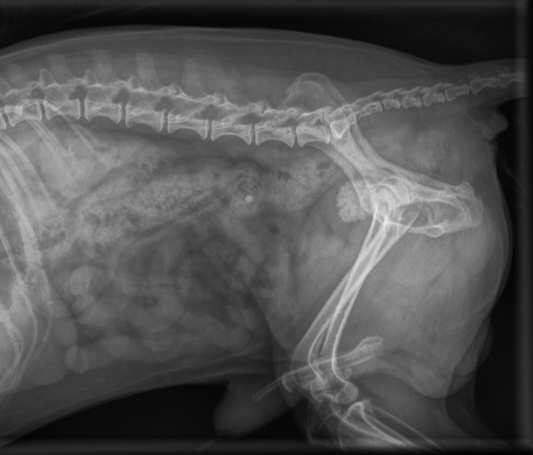

Elokuun kuukauden leikkauspotilaana on pieni Roki. Rokilla oli jo pidempään ollut ajoittaisia virtsaamisvaikeuksia ja virtsarakon ultraäänitutkimuksessa oli havaittu laaja virtsakivi virtsarakossa.

Eläinklinikka Tsempissä Rokin röntgenkuvauksella varmistettiin virtsakiven olevan yhä paikoillaan. Jo röntgenkuvauksella havaittiin, että Rokin virtsarakko sijaitsi epätyypillisen takana ja että virtsarakossa oli yksi hyvin iso ja muhkurainen virtsakivi.

Röntgenkuvassa havaittiin myös Rokin virtsarakon sijaitsevan varsin takana.